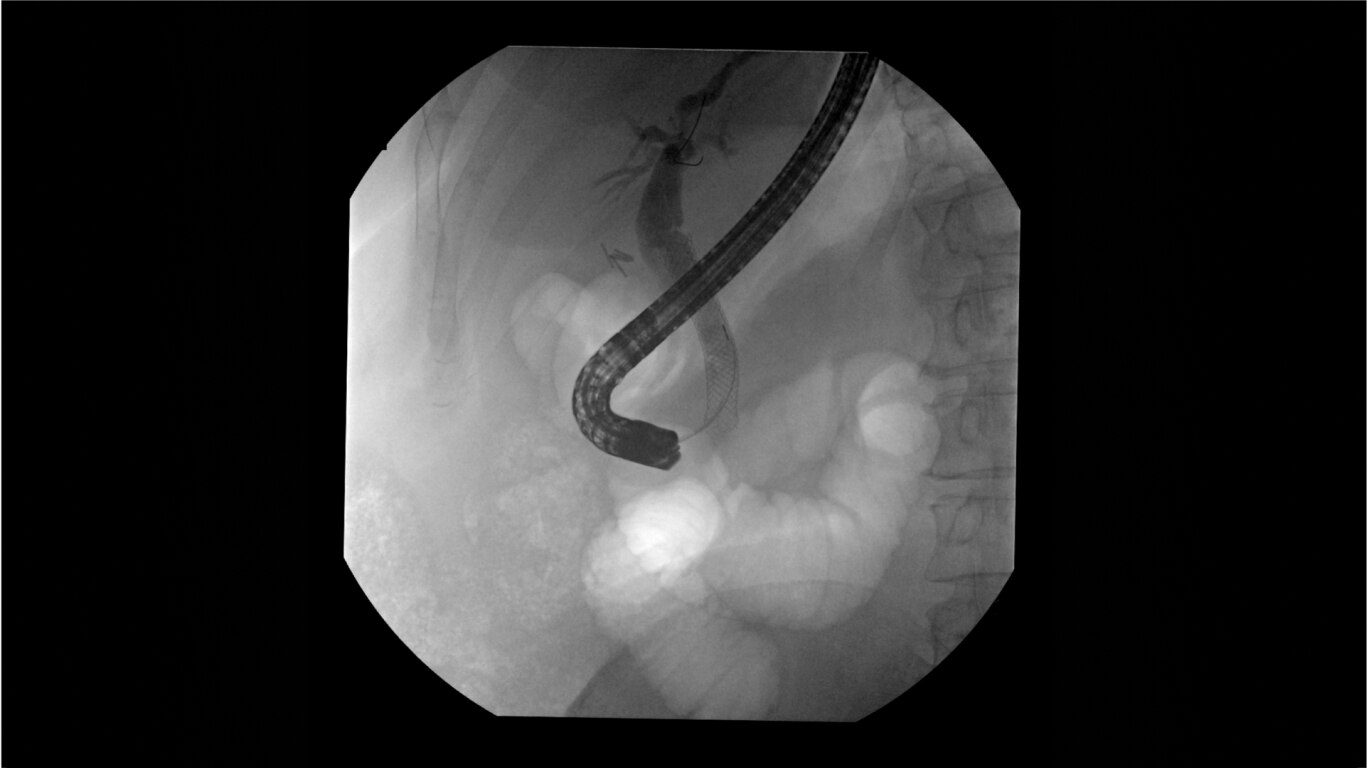

Clearly visualize the GI tract of patients, regardless of size, during a wide range of endoscopic procedures, including ERCP. OEC C-arms offer amazing image quality at low dose and provide enhancements for clear visualization during movement in soft tissue, such as during guidance of low-density drainage tubes or thin biopsy brushes. A large, clear display with comfortable viewing enables effortless workflow.

See detail 1 for 1 from detector to a 4K UHD display for stunning image quality and visualization of low density drainage tubes and thin biopsy brushes.

Complex gastrointestinal procedures require powerful imaging systems. OEC premium C-arms perform in a variety of procedures such as:

• Bariatric gastric embolism

• Pediatric congential duodenal

• Endoscopic retrograde cholangiopancreatography